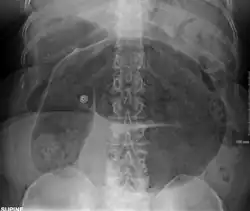

-

Plain X ray of a cecal volvulus -